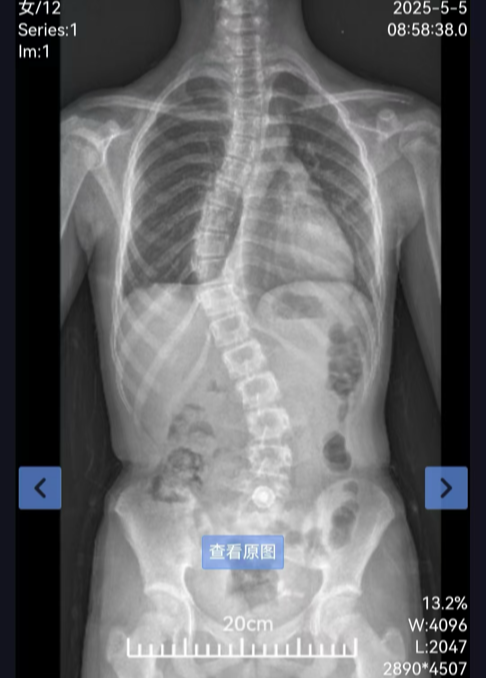

脊柱侧弯:青少年健康的”隐形杀手”

脊柱侧弯是指脊椎出现侧向弯曲,形状可能呈现”S”形或”C”形。这种脊柱畸形已成为继肥胖症、近视之后,威胁我国儿童青少年健康的第三大”杀手”。初期症状往往较为隐匿,但随着病情发展,其危害不容忽视,包括以下几点:

若发现孩子有高低肩、剃刀背、圆肩驼背、骨盆前倾、长短腿等体态异常,或运动易喘、腰背疼痛等症状,应及时进行专业评估。